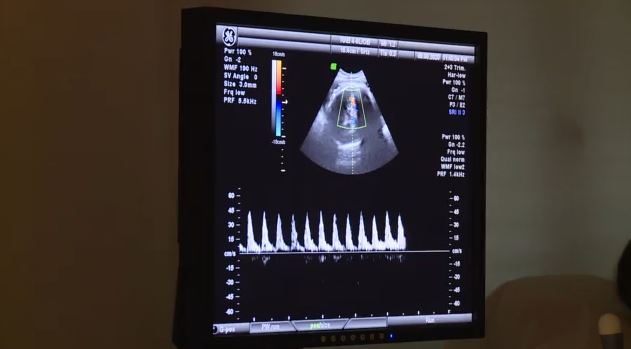

Σύμφωνα με τον ειδικό, «ο εγκέφαλος αντιλαμβάνεται ερεθίσματα που έρχονται από την περιφέρεια. Κατά κανόνα είναι πραγματικά αλλιώς μιλάμε για παραισθήσεις. Απλώς διαφέρει η ένταση. Όταν κάτι συσσωρευτεί και κάνει πολλούς κύκλους αναβολής η διαχείρισή του ή η εκτόνωση του κάποια στιγμή μπορεί να μας «προδώσει». Είναι βασικό να περάσουμε από την περιγραφή του «έχω ένα σύμπτωμα» μέχρι αυτό να γίνει αντικειμενικό και να σου πει κάποιος γιατρός ότι «έχεις δίκιο». Η καρδιολογία είναι η κατεξοχήν ειδικότητα που διαχειρίζεται τον ψυχοσωματικό κίνδυνο. Η ψυχική ένταση ανεβάζει την ένταση με την οποία λειτουργεί το νευρικό μας σύστημα το οποίο καταλήγει σε όργανα και σε αδένες. Βασικοί αδένες γι’ αυτή την ιστορία είναι τα επινεφρίδιά μας που βγάζουν αδρεναλίνη. Όταν έχουμε άγχος ένταση πίεση, όλο το νευρικό μα σύστημα μπαίνει σε κατάσταση έντασης ζώου και η αδρεναλίνη μας μας φέρνει σε κατάσταση πανικού».

«Τα συστήματα που επηρεάζονται πρώτα από τα ψυχοσωματικά είναι το καρδιαγγειακό και έπειτα το γαστρεντερικό, και το δέρμα κοντά σε αυτά. Βοηθάει η εκλογίκευση του συμπτώματος. Εάν επιμένει και αποκτά αντικειμενική διάσταση – που αντικειμενική διάσταση έχει η χρονιότητα – πρέπει να το ψάξουμε. Τα ψυχοσωματικά πρέπει να ερμηνεύονται κυρίως. Κάτι, όταν ξεφεύγει από το συνηθισμένο, πρέπει να το ψάξουμε και να πάρουμε την γνώμη ενός ειδικού, να πάρει κάποιος άλλος την ευθύνη», συνέχισε.